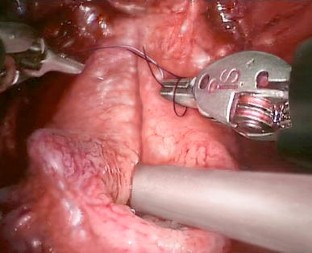

Fig. 3